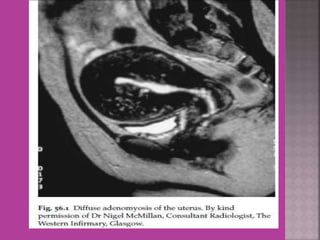

 Adenomyosis---accurate diagnosis.

 MRI is most sensitive for diagnosis of Adenomyosis.

 Study ofnormal uterus and adnexa – with aim to have clear image of normal myometrium, endometrium , ovary and follicles within the ovary.  Myoma—to differentiate myoma from adenomyoma.localization of myoma—sub serous/ intra mural or sub mucous.  Adenomyosis---accurate diagnosis.  Congenital uterovaginal anomalies— bicornuate, septate,subseptate , unicornuate, didelphys ,rudimentary horn and vaginal atrasia etc